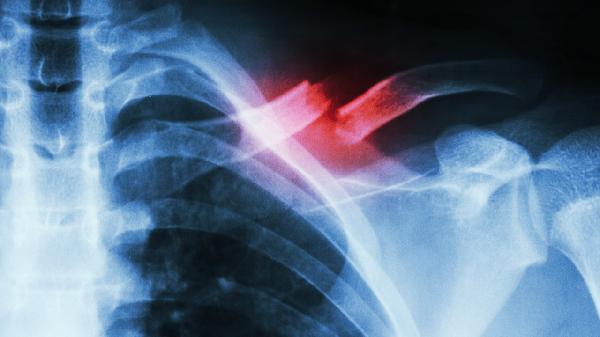

鎖骨骨折后可通過高蛋白食物、富含鈣質食物、維生素D補充、膠原蛋白攝入、鋅元素補充等方式促進骨骼愈合。鎖骨骨折的恢復與營養(yǎng)支持密切相關,合理的飲食結構能加速骨痂形成。

鎖骨骨折恢復期需建立均衡膳食模式,除上述重點營養(yǎng)素外,還應保證新鮮蔬果攝入以提供抗氧化物質。避免高鹽、高糖及含磷碳酸飲料影響鈣代謝,戒煙限酒以防血管收縮阻礙愈合。餐后適當活動促進消化吸收,但需避免患側負重。定期復查X線觀察骨痂生長情況,若出現(xiàn)愈合延遲需在醫(yī)生指導下調(diào)整營養(yǎng)方案。睡眠時保持患肢功能位,配合醫(yī)囑進行漸進式康復訓練,營養(yǎng)與運動結合可顯著提升恢復效果。